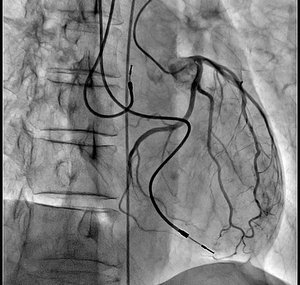

ノイズが少なく明瞭なコントラストで血管が造影される。

下 SCORE PRO Advance 撮影画像 15fps